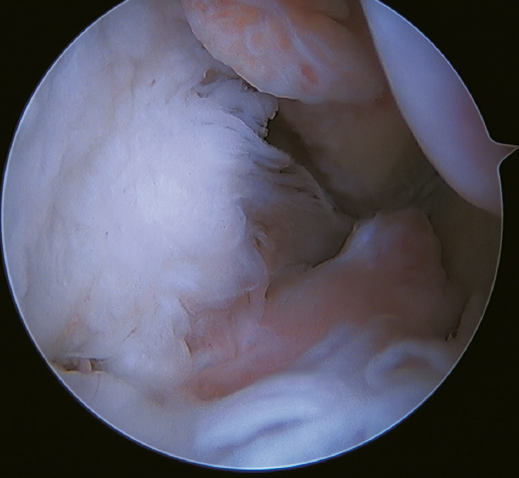

The main indication for this repair is rupture of the upper fascicle of the ATFL from its fibular insertion, with good tissue quality of the remaining ligament (Figure 3).

The technique can be performed through a single modified anterolateral portal or using a third accessory portal. The use of a single portal reduces the risk of injury to the intermediate dorsal cutaneous branch of the superficial peroneal nerve(37). Although there is no difference between the use of one or two implants, the use of two implants implies a larger contact surface(38,39) and improves patient incorporation to sports activities(40,41,42,43,44).